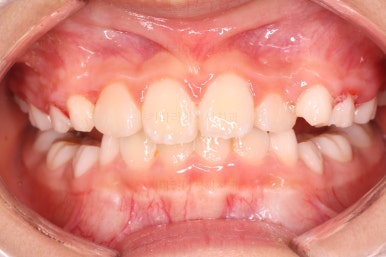

유지단계 4개월째의 모습입니다.

거꾸로 물리는 반대교합이 재발되지 않고 자리를 잘 잡고 있습니다.

위턱뼈가 넓어지다보니 처음에는 삐뚤었던 앞니도 자연스레 자리를 잡아가고 있습니다.

유지단계 11개월 경화 후의 모습입니다. 유지상태는 상당히 좋네요.

이제 유지장치도 종료하기로 하고, 앞으로는 주기적으로 아래턱이 자라나지 않는 지를 체크하게 될거에요.